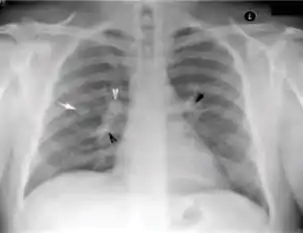

3. Nodule with poorly defined margins - Round density within the lung parenchyma, also called a tuberculoma. Nodules included in this category are those with margins that are indistinct or poorly defined (tree-in-bud sign[3]). The surrounding haziness can be either subtle or readily apparent and suggests coexisting airspace consolidation.

Chest x-ray showing nodule with margins that are indistinct or poorly defined (tree-in-bud sign) in post-primary pulmonary TB.